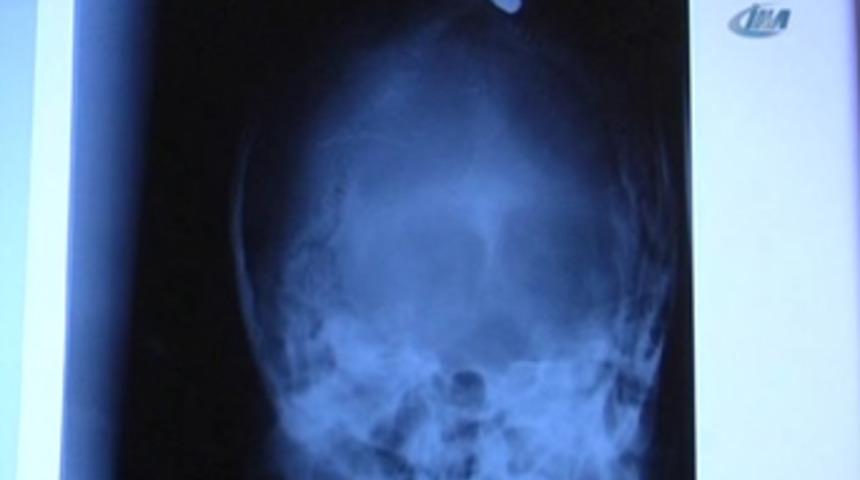

Karacaoğlan Mahallesi 78 nolu sokaktaki evinin damına çıkan Hatice Aslan nereden geldiği bilinmeyen bir kurşunla kafasından yaralandı. Damdan düşen bayan ailesi tarafından hastaneye kaldırıldı. Hatice Aslan'ın röntgenini çeken doktorlar kafa içerisinde mermiyi fark etti.

Ameliyata alınan bayan yapılan müdahalelerin ardından Cerrahi Yoğun Bakım Ünitesi'ne kaldırıldı. Hatice Aslan hayati tehlikeyi atlatamadı. Polis olayla ilgili soruşturmayı sürdürüyor.